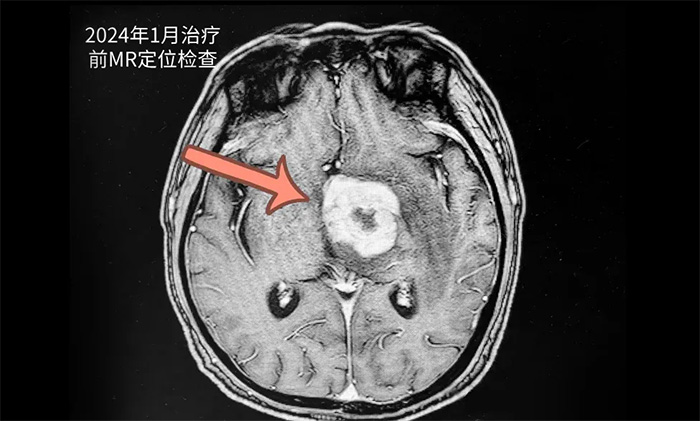

患者秦某(化名)73歲,男性。2023年12月無明顯誘因出現(xiàn)頭暈、頭痛,伴言語不清。于當年12月21日在當?shù)蒯t(yī)院就診,完善相關(guān)檢查MRI示顱內(nèi)占位性病變,顱內(nèi)病灶穿刺活檢病理提示:高侵襲性B細胞淋巴瘤。后患者來到上海藍十字腦科醫(yī)院尋求進一步治療。

▲ 治療前影像

王曉東主任團隊為患者完善各項檢查。根據(jù)患者的臨床資料、病理診斷和影像結(jié)果,明確患者滿足放療條件,并制定了完善周密的放療計劃。為患者開展20次放射治療。歷時約1個月完成治療后,患者頭暈、頭痛,伴言語不清等癥狀有了不同程度改善。復(fù)查頭顱MR,可見病灶范圍明顯縮小。